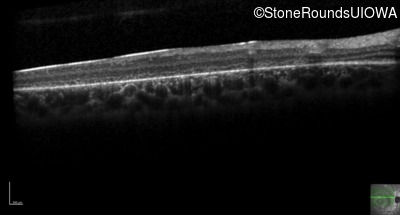

Optical Coherence Tomography - Right - 20/200 -3

Exemplar / OCT Stack